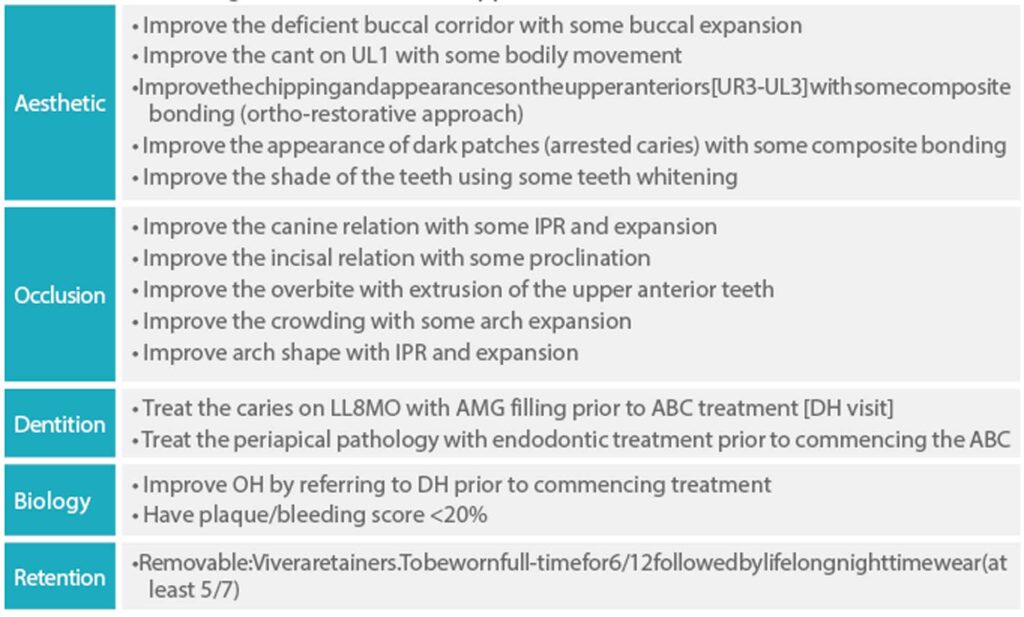

The scope of the treatment goals achievable were presented to the patient with advantages and disadvantages of the alternative treatment plans. The treatment goals (listed in Table 2) were agreed and defined.

Table 2: Treatment goal (non-extraction approach)